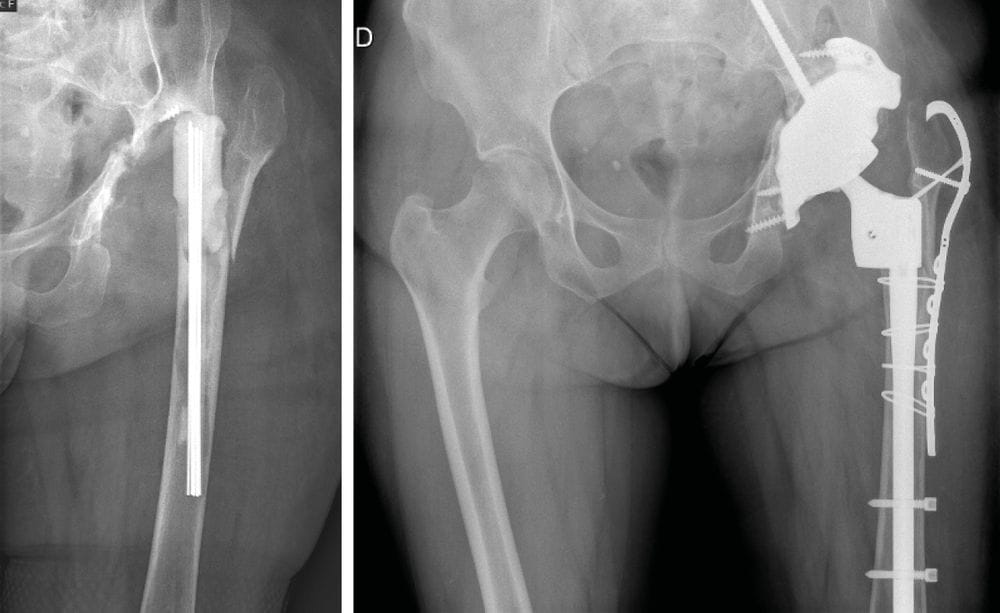

Case report n°1 (Figure 1)

- PPF at the cementless pivot (Vancouver B2)

- Two component revision: cementless monoblock long stem non-locking, fracture repair with cerclage wiring

- Dual mobility cup

Case report n°2 (Figure 2)

PPF at the cementless pivot (Vancouver B2) after acetabulum-only revision

Femur-only revision: cementless monoblock long stem Locking stem, fracture repair with cerclage wiring.